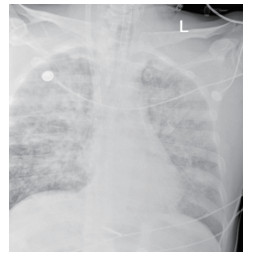

1.2 临床表现和检查患者初期有咳嗽症状,但未在意,患者回家24 h后咳嗽症状加重,伴胸闷气喘,全身大汗淋漓,家属立即将其送至本院急诊,为进一步诊治拟“有机氟中毒”收住入院。入院时体检:神志清楚,T:36.5℃,R: 57次/min,BP: 146/71 mmHg,胸廓对称无畸形,呼吸急促,听诊双肺呼吸音清晰,可闻及大量湿性啰音,心率112次/min,心律齐,心音正常,各瓣膜听诊区未闻及病理性杂音及心包摩擦音,四肢关节正常,双下肢无水肿,深浅生理反射正常,病理反射阴性,脑膜刺激征阴性。辅助检查:白细胞计数10.45×109/L,中性粒细胞91.9%;C-反应蛋白14.81 mg/L, 无创机械通气支持下血气分析pH7.28,PCO2 50 mmHg, PO2 57 mmHg, Lac 3.0 mmol/L(FiO2 50%),为Ⅱ型呼吸衰竭,给予无创呼吸机辅助呼吸、激素冲击、解痉平喘等抢救治疗。急诊胸部CT检查提示:两肺散在斑片状模糊影,密度不均,边界不清(图 1),进ICU床边胸片提示:两肺散在斑片状模糊影(图 2)。根据GBZ5—2016《职业性氟及其无机化合物中毒的诊断》的诊断标准,该患者诊断为职业性急性重度有机氟中毒。

| 图 2 3月10日胸部X线 |